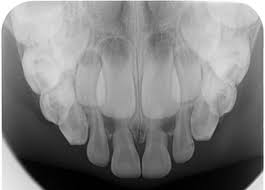

Panoramic X-ray

เพื่อภาพรวมของฟันทั้งหมด